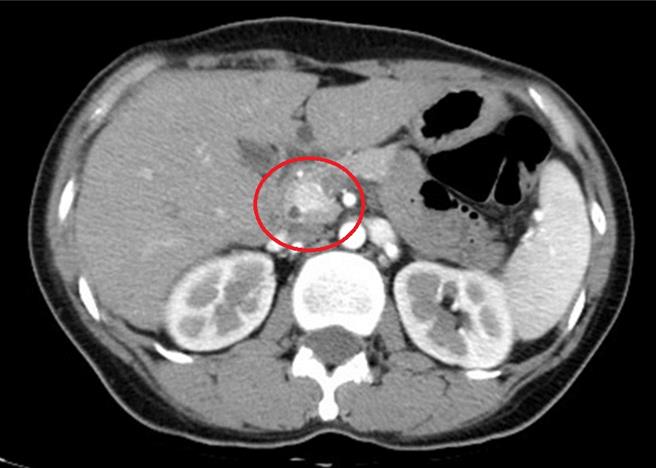

亚洲大学附属医院新陈代谢科医师王子源表示,透过腹部断层扫描察觉胰臟异状。(亚大医院提供/冯惠宜台中传真)

王子源说,直到半年后患者到诊所健康检查抽血,发现严重低血糖,经转介来门诊寻找病因,由于过去曾诊疗过类似病例,综合前述异常举止及自发性低血糖等症状,怀疑恐是罕见的「胰岛素瘤」,于是安排病患住院检查,也透过腹部电脑断层及内视镜超音波检查,发现胰臟的头部有一颗约1.4公分的肿瘤。